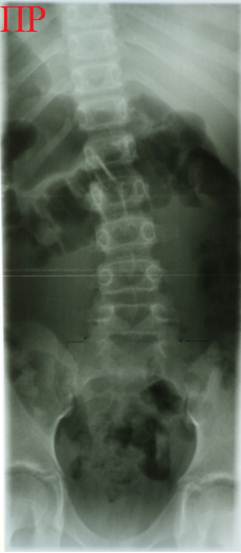

Снимки

детей 6 - 7 лет с впервые выявленным нарушением фронтальной осанки – «плывущей»

спиной, Slide – Shift. Снимки не расчерчены, угол деформации на них

не превышает 5-6 градусов. Снимки чётко раскрывают суть явления: некомпенсированная деформация

позвоночника в верхней части поясничного отдела без структурных изменений в

позвонках. Грудной отдел позвоночника не

деформирован, потому что он хорошо армируется структурами грудной клетки -

ребрами, грудиной. Грудная клетка балансирует на гибком поясничном отделе

позвоночника при помощи мышц поясницы и спины. У детей, чьи снимки

представлены, процесс балансировки определенно нарушен. Обратите внимание, что

в большинстве случаев Slide – Shift и вершина

основной дуги направлены в правую сторону.